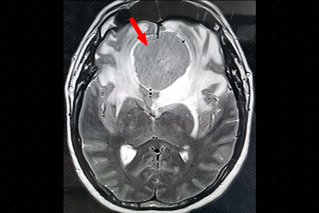

Texto alternativo para a imagem Figura 3. Créditos: Dra. Elazir Mota - Rio de Janeiro/RJ

Descrição da figura 3: Coronal, T1 pós-contraste. Lesão apresenta marcado realce homogêneo pós-contraste (seta vermelha).